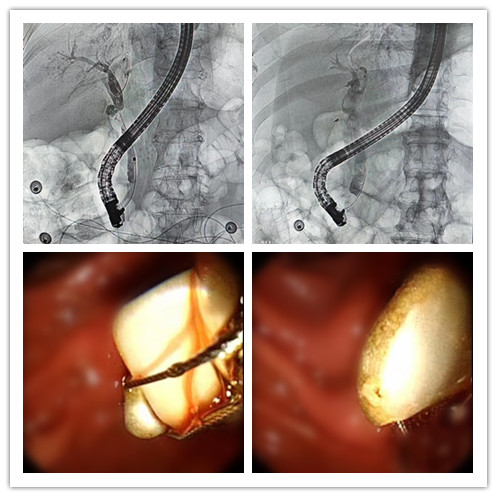

檢查結(jié)果顯示他的膽道梗阻嚴(yán)重,膽總管內(nèi)有10余枚“巨大”白色膽固醇結(jié)石,其中最大的結(jié)石大小約為1.5cm*2.0cm,相當(dāng)于一顆葡萄的大小。與常見的綠色膽色素結(jié)石和黃色膽固醇結(jié)石,蛋白或鈣化結(jié)石不同,無膽胰合流異常。

“ERCP與傳統(tǒng)外科手術(shù)相比較,具有微創(chuàng)、痛苦少、恢復(fù)快等優(yōu)勢,即使結(jié)石復(fù)發(fā),仍可重復(fù)取石,是目前治療膽總管結(jié)石的良好方法。”牛昊書充分與患者及其家屬講解手術(shù)過程及風(fēng)險,患方同意配合診療方案。最終,白先生的ERCP手術(shù)十分順利,10余枚結(jié)石在膽總管間“閃-轉(zhuǎn)-騰-挪”一次全部取出,解除了膽道梗阻。術(shù)后患者恢復(fù)良好。